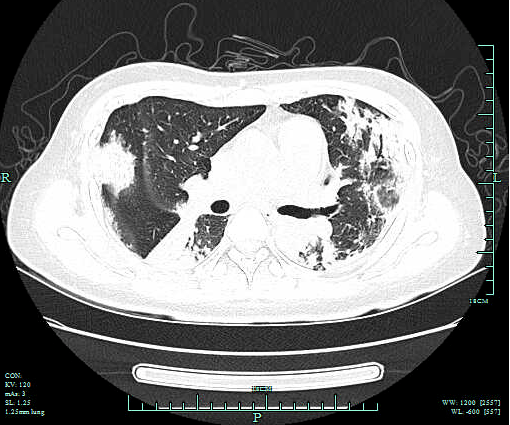

李琴(化名) , 女 , 47岁 , 因间断发热10天 , 胸闷、气喘加重1天收 住我院呼吸重症监护室 。 入院肺部CT提示两肺上叶、下叶背段多发感染 , 左肺下叶少许间质纤维化伴间质性炎症 , 两侧胸腔积液 。 入院予以无创辅助通气(高流量氧支持) ,积极抗感染、补液、纠正内环境等对症支持治疗 , 效果欠佳 , 在院期间完善痰、尿、便检验及院外肺泡灌洗液NGS , 均未寻找到可靠病原学依据来指导临床 。鉴于患者病情危重 , 治疗效果不理想 , 感染病因难以明确 , 预后较差 , 经 家属同意 , 医师在床旁行“超声定位引导下右肺穿刺活检术” , 后期 随访病理诊断:机化性肺炎 。 后经系统治疗患者临床症状改善 , 好转出院 。